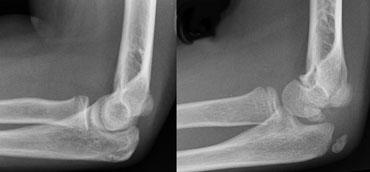

Supracondylar fractures. In A the anterior humeral line passes through the anterior third of the capitellum and in B even more anteriorly. Notice positive posterior fat pad sign in both cases

Gãy xương trên lồi cầu (2)

Nếu chỉ có di lệch tối thiểu hoặc không có di lệch, các gãy xương này có thể ẩn trên phim X-quang.

Dấu hiệu duy nhất sẽ là dấu hiệu đệm mỡ dương tính.

Thường có một số di lệch và đường cánh tay trước sẽ không đi qua trung tâm của chỏm con mà đi qua một phần ba trước hoặc thậm chí phía trước chỏm con (hình).

Gãy xương trên lồi cầu (3)

Gãy xương trên lồi cầu được phân loại theo Gartland.

Gãy xương loại I theo Gartland thường khó nhìn thấy trên X-quang do chỉ có di lệch tối thiểu.

Hầu hết các gãy xương này bao gồm gãy xương kiểu cành xanh hoặc gãy xương kiểu vỏ cây.

Dấu hiệu duy nhất gợi ý chẩn đoán có thể là dấu hiệu đệm mỡ dương tính.

Những bệnh nhân này được điều trị bằng bó bột.

Trong gãy xương loại II theo Gartland, có sự di lệch nhưng vỏ xương phía sau vẫn còn nguyên vẹn.

Có thể có một số xoay. Những gãy xương này cần nắn chỉnh kín và một số trường hợp cần cố định xuyên da nếu bột dài cánh tay không giữ được kết quả nắn chỉnh một cách thỏa đáng.

Gãy xương loại III theo Gartland là gãy xương di lệch hoàn toàn và có nguy cơ liền xương lệch và biến chứng thần kinh mạch máu (hình).

Những trường hợp này cần được nắn chỉnh bằng phương pháp kín hoặc nếu cần thiết bằng phương pháp mổ hở. Cố định được duy trì bằng hai đinh bên ngoài hoặc kỹ thuật đinh chéo trong-ngoài.